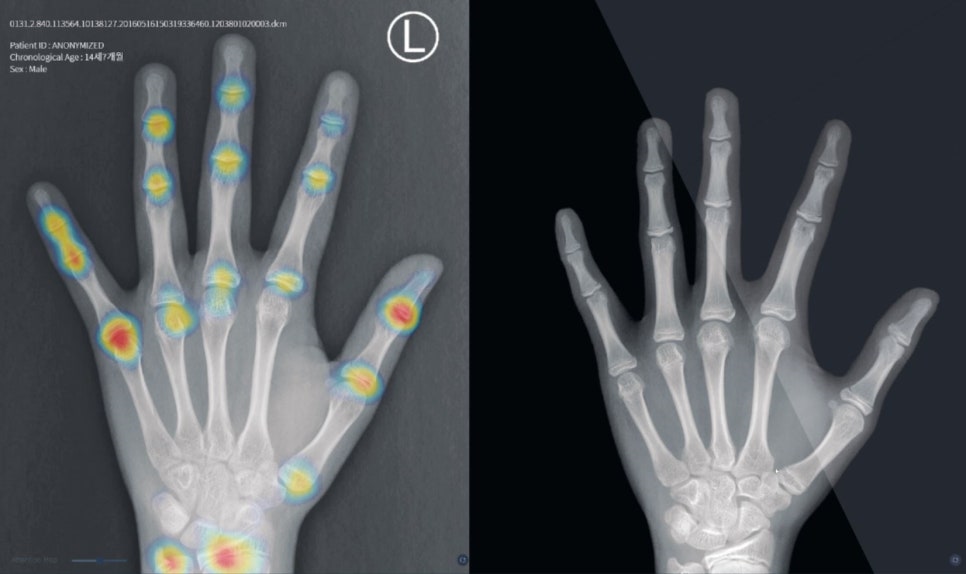

![연세굿데이치과] 성장판 검사가 중요한 이유 관련 이미지 3](https://pub-9f2bb3498faf4d1d8714b41df24753e3.r2.dev/content/clinics/archive/5hurea2jnb/naver_blog/eunkyo3370/assets/by_hash/596b72370ddac4e3255aa5125fc9c991e7ecde48642960a5ad230acd26a5d0fd.jpg)

(열린 성장판)